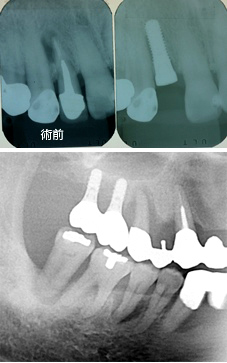

御存知の通り「インプラント治療」とはチタン合金のネジを顎骨に埋めて、その上に「歯」のようなものを載せ、その「人工の歯」を使って咀嚼を助ける治療のことです。「歯が1本抜けたらインプラントを1本埋める」のように1対1が理想です。インプラントが使われるまでは「ブリッジ」という治療法が一般的でした。なぜ「一般的」なのかと言えば、選択肢が取り外し式の「入れ歯」か、固定式の「ブリッジ」しかなかったからです。「入れ歯」は患者さんに嫌われました。下顎の入れ歯の場合は食事中に外れやすく、入れ歯の一部が舌の先が当たって邪魔なので、入れ歯を作ってもほとんど使われません。しかし、過大な咬合力が長期間小臼歯に懸かると徐々に歯を壊していきます。神経の死んでいる歯の場合は必ず折れます。小臼歯まで無くなればさすがに食事は困難を極めます。お友達と食事に行けば、いくら急いで食べても食べ終わるのは最後です。咀嚼せずに飲み込むので常に胃腸の具合が悪く、消化薬を常用しています。唯一の救いは、お友達と一緒に旅行に行ったときに入れ歯を外すところを見られずに済むことぐらいでしょうか。正面からの見た目だけは維持されますから、なんとか我慢できるのでしょう。

御存知の通り「インプラント治療」とはチタン合金のネジを顎骨に埋めて、その上に「歯」のようなものを載せ、その「人工の歯」を使って咀嚼を助ける治療のことです。できれば「1本歯が抜けたら1本インプラントを埋める」ように1対1の方法が理想です。インプラントが出るまではブリッジという治療法が一般的でした。選択肢が取り外し式の「入れ歯」か、固定式のブリッジしかなかったからです。しかし、一番後ろの歯がなくなると入れ歯しかありませんでした。特に下顎の入れ歯の場合は食事中に外れやすく、入れ歯の一部が舌の先が当たって邪魔なので、入れ歯を使わなくても食事できる場合はほとんど使われません。大臼歯2本無くても充分に食事はできます。しかし、過大な咬合力が長期間小臼歯に懸かると徐々に歯を壊していきます。生きている歯は折れることはありませんが、神経の死んでいる歯の場合は必ず折れます。小臼歯も無くなればさすがに食事は難しくなります。お友達と食事に行けば、急いで食べても食べ終わるのは最後です。そして常に胃腸の具合が悪く、消化薬を常用しています。唯一の救いは、お友達と一緒に旅行に行ったときに入れ歯を外すところを見られずに済むことぐらいでしょうか。正面からの見た目だけは維持されますから、なんとか我慢できるのでしょう。斜め45度じゃバレます。

近頃のレーシックの感染事件のように歯周病の治療もできないのに、安易にインプラントを取り入れてお金だけ集めている歯医者もいるように聞きます。残っている歯を管理できないのに新しく「歯」を入れるなんて無謀な話です。実際にインプラントを他の歯科医院で受けて歯周病の管理もされずに崩壊直前の状態の方も時々見かけます。全ては「始めに口腔内衛生の確立ありき」なのです。まずは歯周病の除去です。そして良い環境の維持、定期検診(PMTC)です。インプラントを埋めるよりも遙かに大変な作業です。安売りインプラントは保証もメンテも付いていないから安いのです。

すでに1000本以上(もうわからなくなりました)、19年の経験の中で大切なことがいくつか見えてきました。ひとつはハイリスクな患者さんがいることです。これは歯周病のリスクと近いものがあります。喫煙、歯周病、糖尿病などです。二つ目は埋める場所が無い人がいることです。その場合、大がかりな手術が必要になります。失敗する可能性も出てきます。三つ目は噛む力のコントロールが難しい。咬合力が出るので、反対側の歯を壊してしまう可能性があります。対合歯が入れ歯の場合、顎の骨の吸収が早くなり,入れ歯が不安定になります。四つ目は噛み合わせの問題が出てくる可能性が高くなります。今までは入れ歯だから適当に外れたりして問題が深刻化しなかったのですが、インプラントの場合は脱落がありません。だから、常に咬むことで24時間筋肉の異常が起こり、咬合に起因する問題を起こす可能性が高くなります。まあ、噛み合わせの問題はインプラントだけの問題じゃありませんけど・・・。